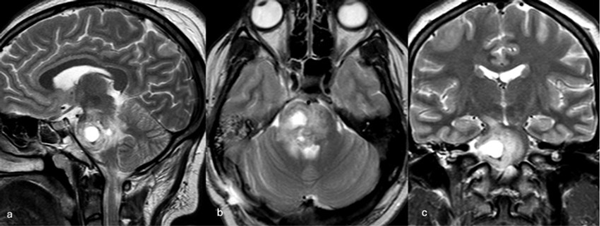

Figura 6. RM preoperatoria de encéfalo. Se evidencia una lesión única intraaxial localizada en el puente y pedúnculo cerebeloso medio izquierdo, hiperintensa en T1 y con un anillo hipointenso en T2, característica de una malformación cavernomatosa con sangrado reciente. A) Imagen ponderada en T1 en corte sagital. B y C) Imágenes ponderadas en T2 en cortes axial y coronal, respectivamente.